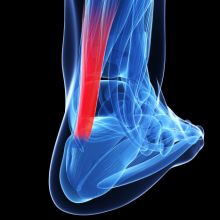

Bolest Achillovy šlachy